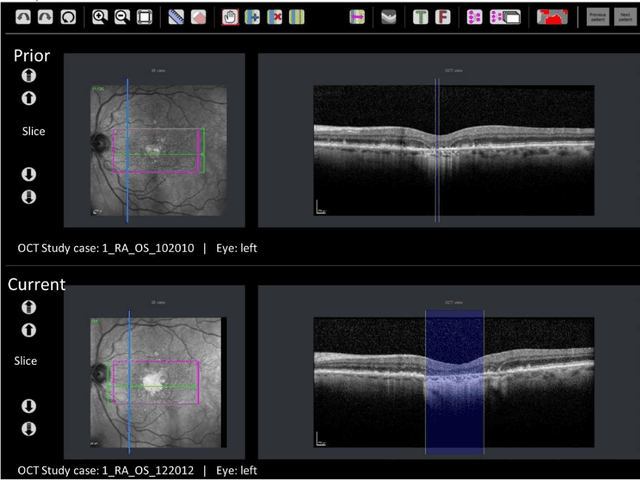

Abstract:Purpose: Disease progression of retinal atrophy associated with AMD requires the accurate quantification of the retinal atrophy changes on longitudinal OCT studies. It is based on finding, comparing, and delineating subtle atrophy changes on consecutive pairs (prior and current) of unregistered OCT scans. Methods: We present a fully automatic end-to-end pipeline for the simultaneous detection and quantification of time-related atrophy changes associated with dry AMD in pairs of OCT scans of a patient. It uses a novel simultaneous multi-channel column-based deep learning model trained on registered pairs of OCT scans that concurrently detects and segments retinal atrophy segments in consecutive OCT scans by classifying light scattering patterns in matched pairs of vertical pixel-wide columns (A-scans) in registered prior and current OCT slices (B-scans). Results: Experimental results on 4,040 OCT slices with 5.2M columns from 40 scans pairs of 18 patients (66% training/validation, 33% testing) with 24.13+-14.0 months apart in which Complete RPE and Outer Retinal Atrophy (cRORA) was identified in 1,998 OCT slices (735 atrophy lesions from 3,732 segments, 0.45M columns) yield a mean atrophy segments detection precision, recall of 0.90+-0.09, 0.95+-0.06 and 0.74+-0.18, 0.94+-0.12 for atrophy lesions with AUC=0.897, all above observer variability. Simultaneous classification outperforms standalone classification precision and recall by 30+-62% and 27+-0% for atrophy segments and lesions. Conclusions: simultaneous column-based detection and quantification of retinal atrophy changes associated with AMD is accurate and outperforms standalone classification methods. Translational relevance: an automatic and efficient way to detect and quantify retinal atrophy changes associated with AMD.